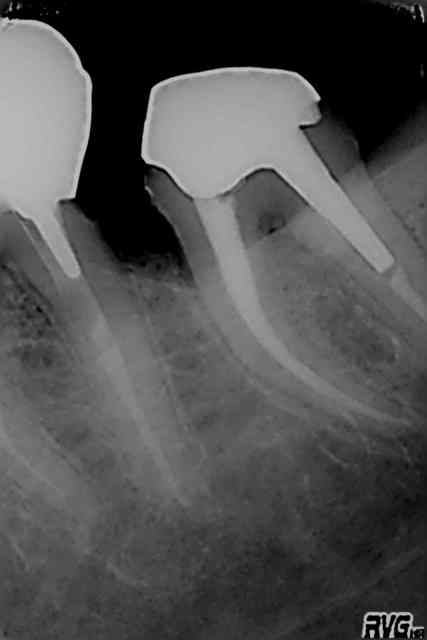

Sx protaper, largo numero 3, re sx pour se rapprocher de l'apex puis s1, s2, f1 f2 protapers. Depuis 4 mois j'ai remplacé s2, f1 f2 par r25 réciproc voir r40.

Ce matin finition r40, pas d'empreinte pour ic, je ne disposais que d'une demi-heure et devis non établi.

Fuck j'arrive pas à virer la radio avec l'inlay core.

J'aime bien le IC sur la pré-molaire

1. c'est une 6, 2. c'est pas une de mes réalisations et ça a au moins 12 ans, comme quoi !